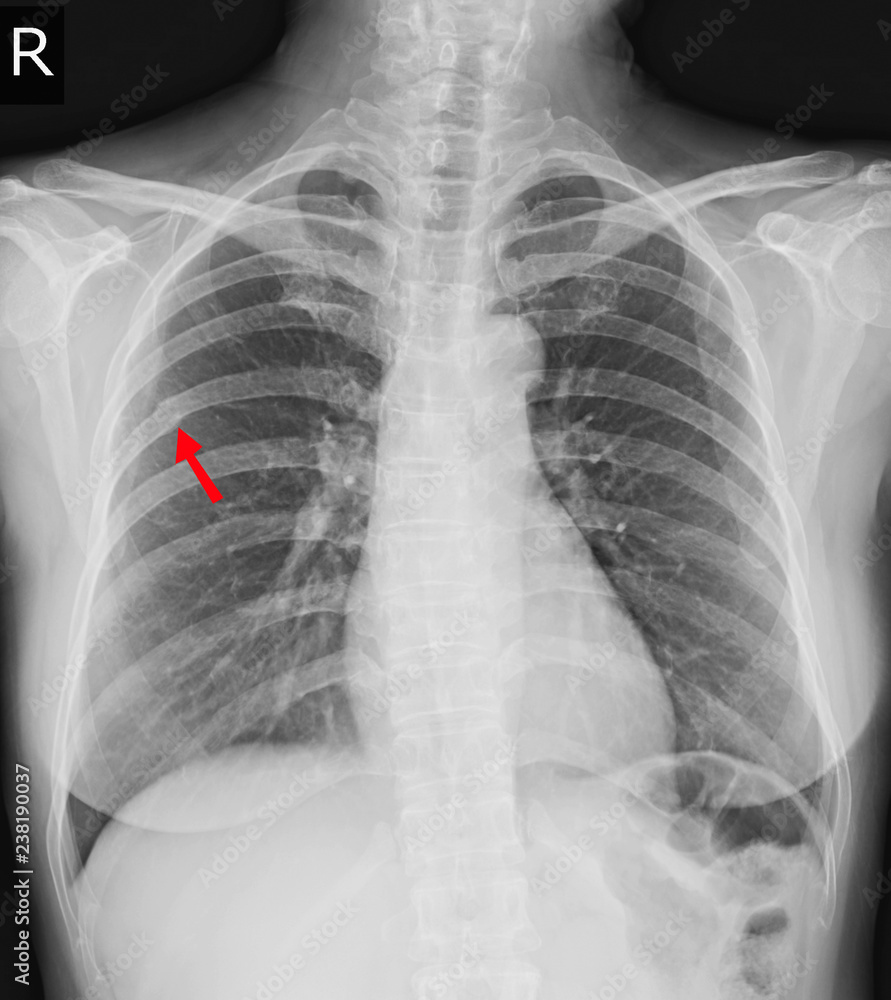

Chest xray Fracture right posterior 6th rib and possible fracture

Chest xray Fracture right posterior 6th rib and possible fracture Rib Fracture Definition Wikipedia  Learn about symptoms and treatment. Left pleura cavity (viewed from left) showing intercostal bundles (vein, artery, and nerve) under ribs.   rib fractures occur when a significant enough force directed at the rib causes a break. Rib fractures are common injuries that most. There are a total of 12 pairs of ribs in the thoracic region. Most common injury in. Rib Fracture Definition Wikipedia.